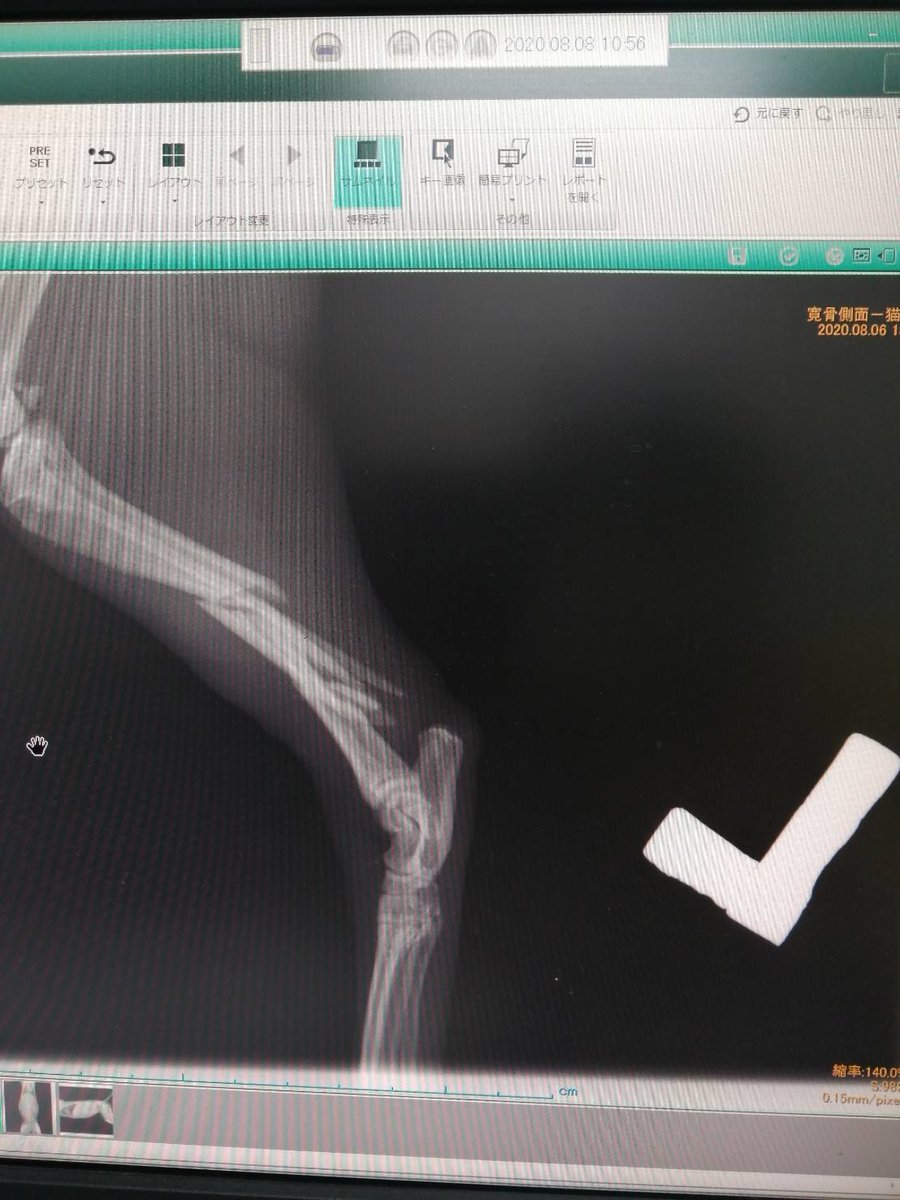

久留米で複雑骨折の子が保護されています。 とてもきれいな子 この子をごぞんじの方いらっしゃいませんか